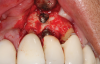

In this case, a dental implant that had been placed 10 years prior was functional, stable, and esthetically acceptable to the patient. However, a significant fistula was present on the facial-apical aspect of the ridge in the maxillary lateral incisor area. This area was painfully sensitive to touch and demonstrated purulence when squeezed. To evaluate the lesion, first, a conventional digital radiograph was acquired, which revealed an apical radiolucency at the apex of the implant (Figure 1). Further analysis using cone-beam computed tomography (CBCT) demonstrated a fistula from that site to the oral environment (Figure 2). Treatment options were discussed, including removal of the implant, followed by grafting, a healing period, and replacement of the implant and implant-retained crown. If this option was selected, a transitional appliance would need to be created. Another option was to attempt to salvage the implant and implant crown by treating the infection and grafting the site to create a new boney wall and eliminate the fistula. Ultimately, the patient accepted this option to attempt to salvage the fixture and crown.

(1.) Preoperative radiographic evaluation demonstrating a large radiolucency at the apical third of the body of an implant fixture replacing the patient’s maxillary left lateral incisor. The implant was stable, and the prosthesis was deemed esthetically acceptable by the patient.

Figure 1